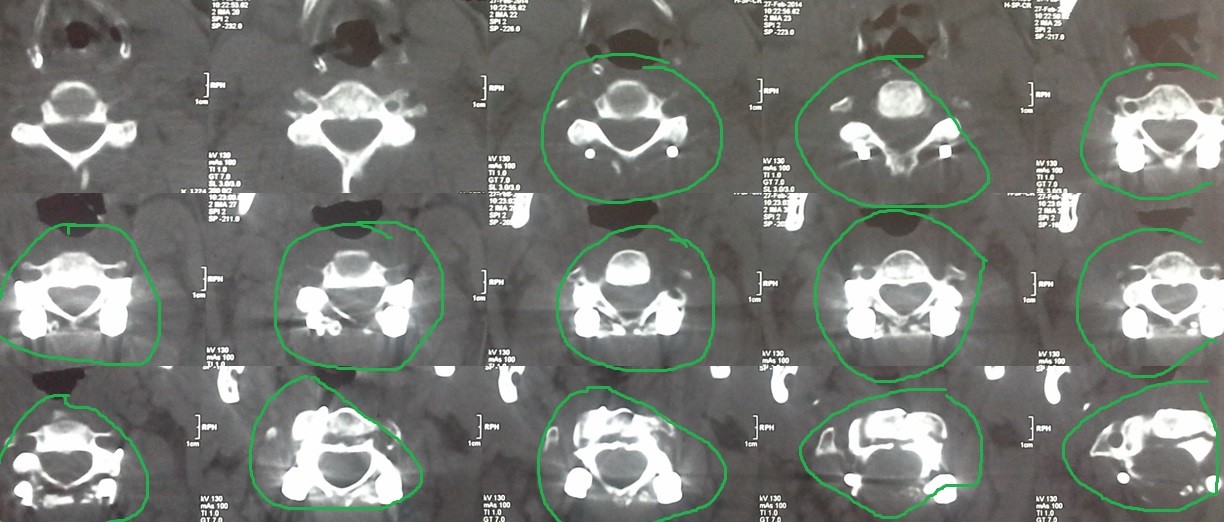

fracture of the second cervical vertebra with displacement between the second and third cervical